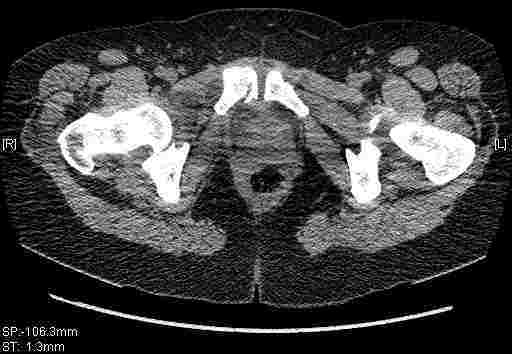

Удалось сегодня вывести пациентку в соседнюю больницу, где есть кт. Срезы сделаны только горизонтальные.